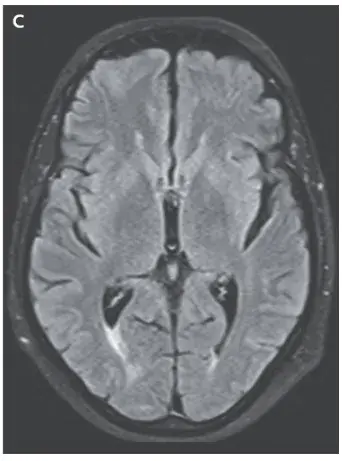

La resonancia magnética (RM) cerebral ponderada en T2 mostró una señal hiperintensa en la sustancia blanca cortical y subcortical, hallazgos consistentes con **edema vasogénico** (imágenes A y B). Los hallazgos de la angiografía por RM arterial y venosa fueron normales.

Se retiró el medicamento (ciclosporina) y los síntomas del paciente y los hallazgos de la resonancia magnética se resolvieron (Imagen C).